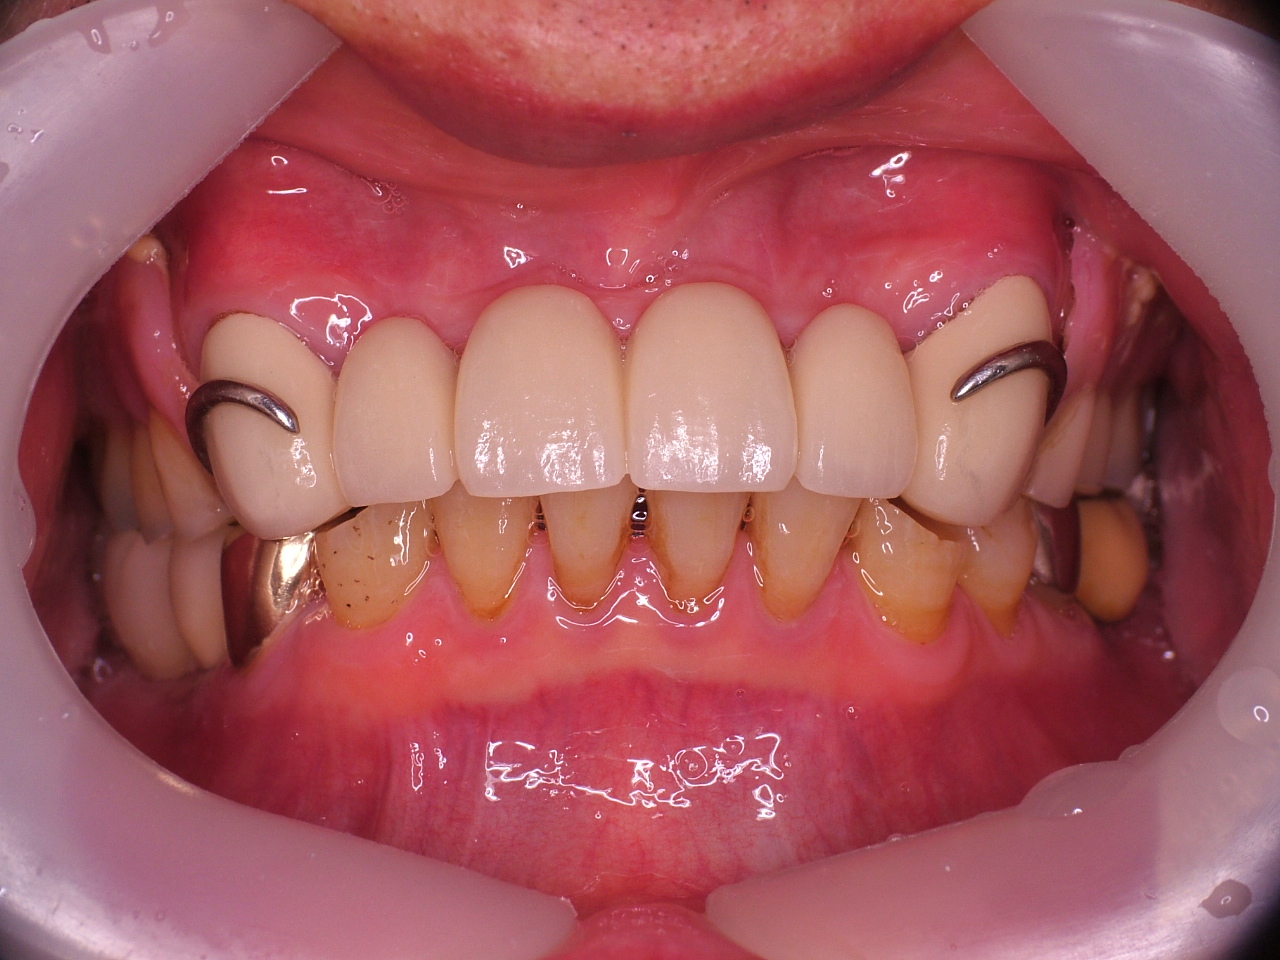

[임플란트] 제목 : 상악 전악 및 하악 구치부

틀니를 벗고 임플란트로